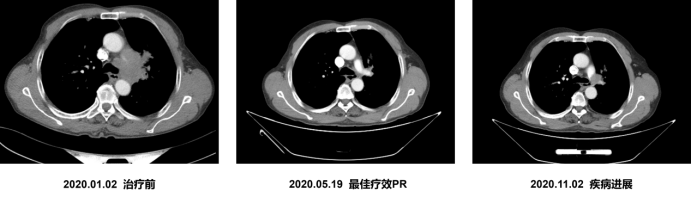

治疗经过

2020.01.13起阿得贝利单抗+EC治疗6周期

2020.04.08门诊胸部CT检查,疗效评估为PR

2020.06.30起阿得贝利单抗单药维持6周期

2020.11.02门诊胸部CT检查,疗效评估为PD

2022.09 患者死亡,总生存期长达32个月

疗效评估